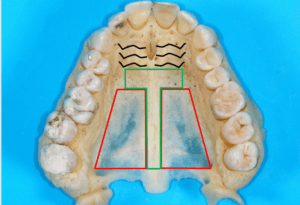

For the stability and predictability of the mini-implants (TADs), we need to place them in the areas with the best cortical bone quality. Several CBCT studies have shown that this is in the anterior palate along an area designated as the T-Zone (Fig. 3).27-29